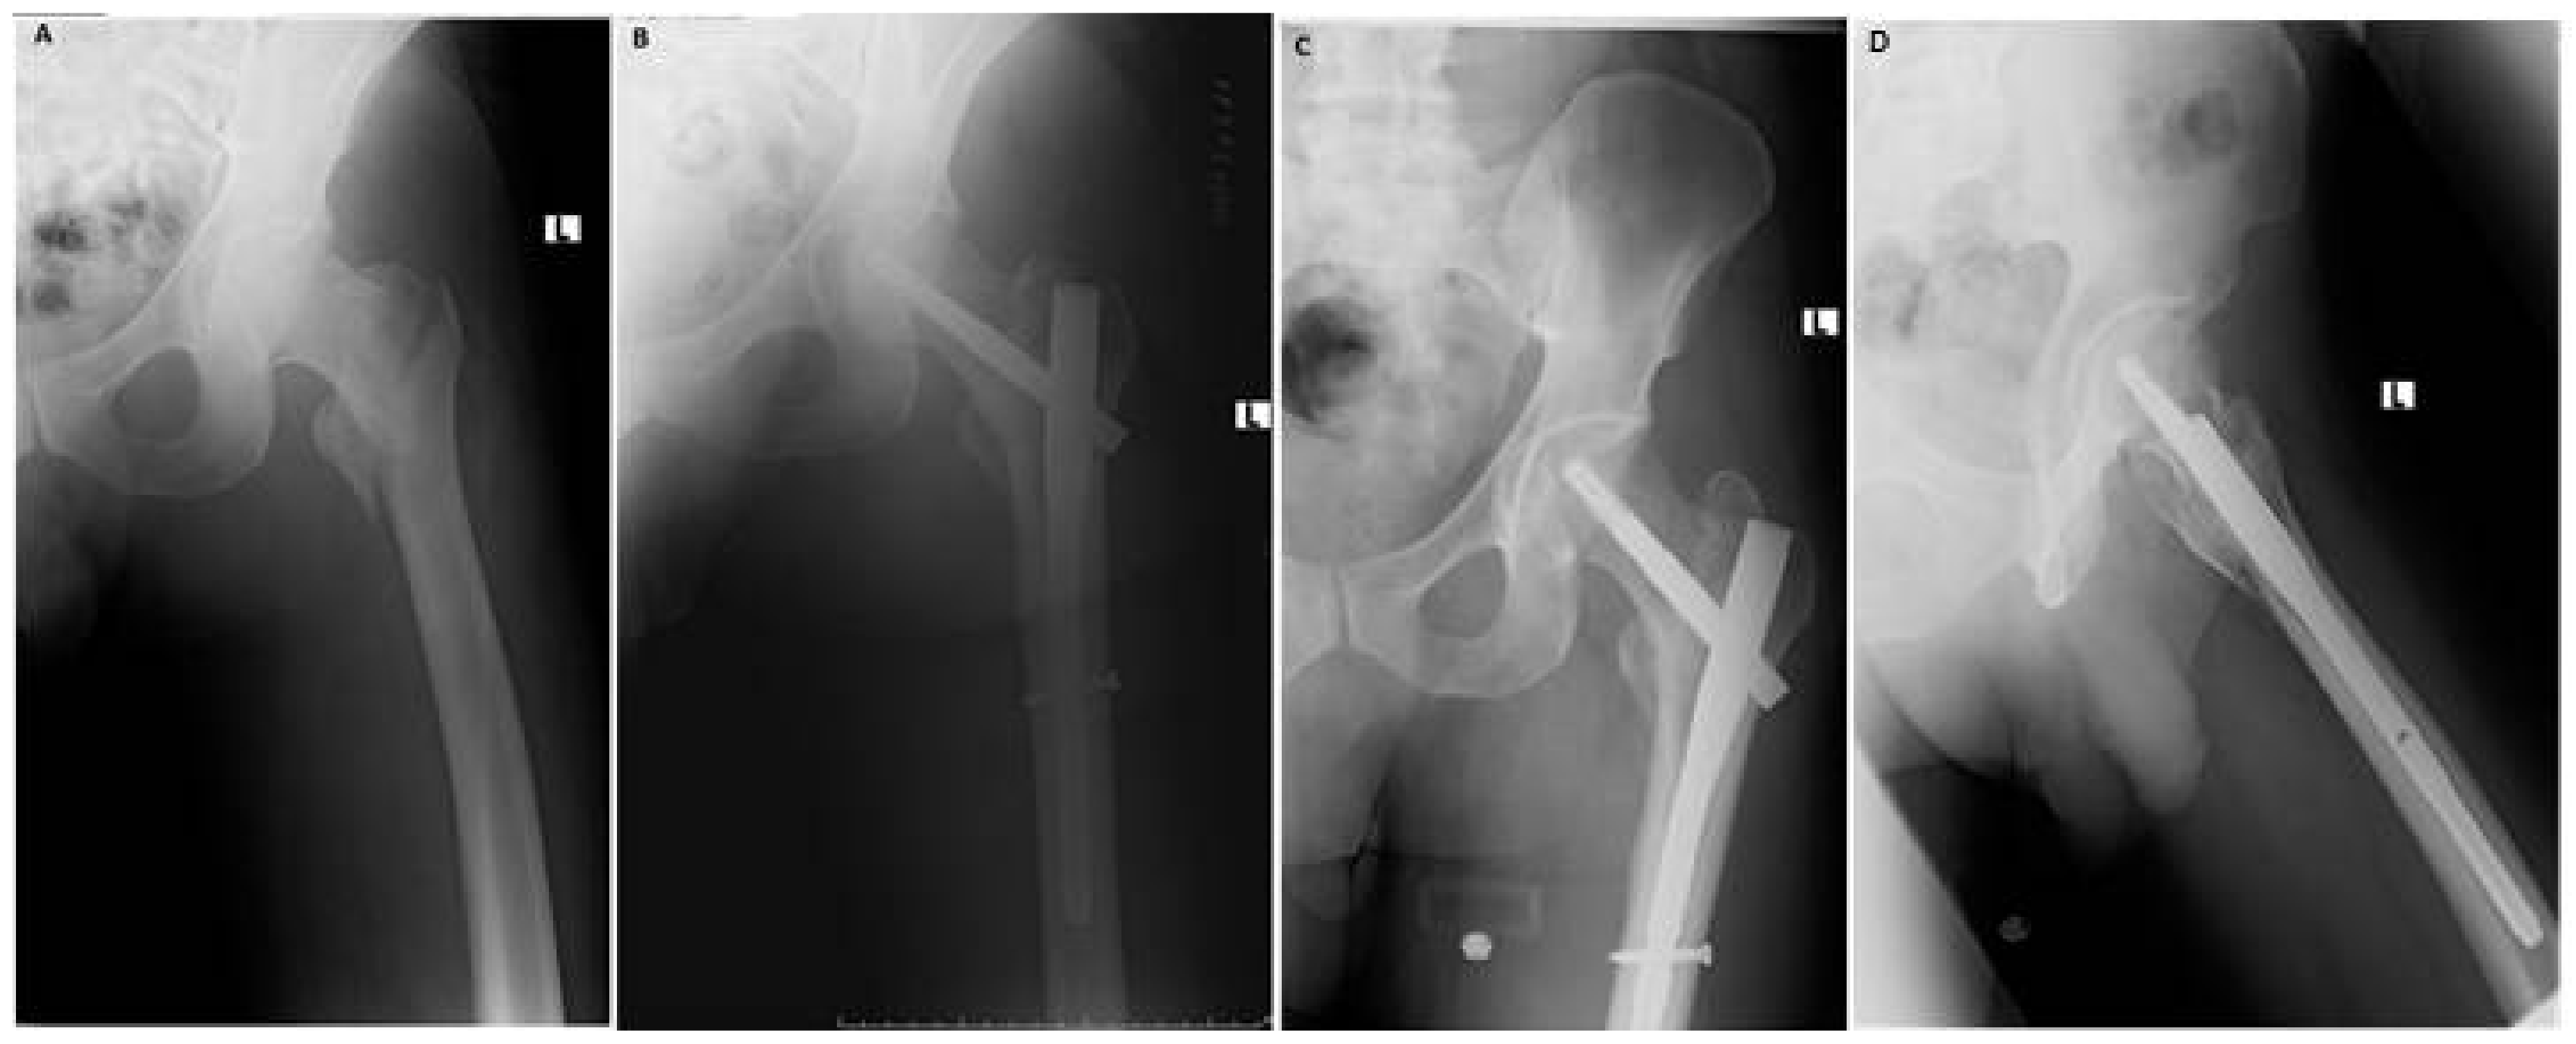

Functional and Radiological Results of Proximal Femoral Nail Antirotation (PFNA) Osteosynthesis in the Treatment of Unstable Pertrochanteric Fractures

2. Experimental Section

3. Results